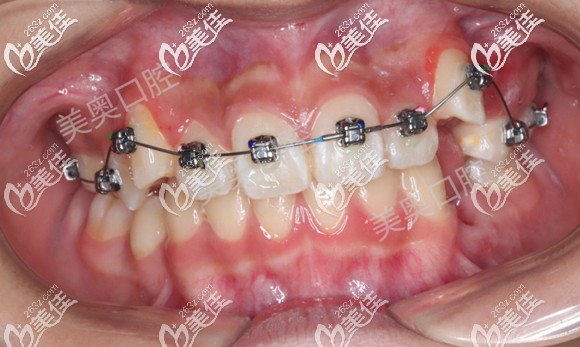

上圖是男孩上牙矯治6個(gè)月,下牙矯治4個(gè)月的效果,可以看到牙齒明顯有所排齊。